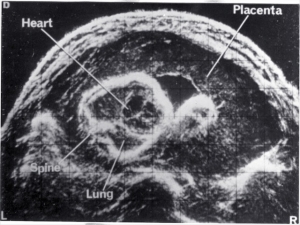

- Fetal anatomy

| 1968 | Demonstration of fetal orbits, heart, bladder, kidneys and scrotum |

| 1970 | Introduction of grey scale ultrasound, improving dramatically the demonstration of normal and abnormal structures in the fetus, placenta and mother |

| 1980 | Demonstration of fetal lung, liver and bowel maturation by grey scale ultrasound |